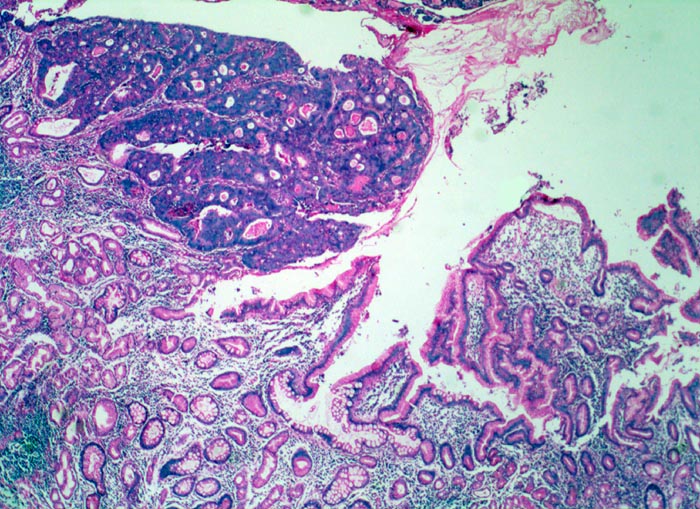

Bei Magenfrühkarzinomen findet sich häufiger ein intestinaler als ein diffuser Typ nach Lauren (Magenkarzinom vom diffusen Typ siehe Differentialdiagnose). Beim intestinalen Typ ist das Tumorgewebe relativ scharf gegenüber der Umgebung abgegrenzt und zeigt meist tubuläre Tumorformationen, die von Zylinderepithel ausgekleidet werden. In der Nachbarschaft von Magenkarzinomen des intestinalen Typs finden sich gehäuft Dysplasien als sogenannte Ausläuferläsionen oder schwere Formen der chronisch atrophen Gastritis mit intestinaler Metaplasie ( 1302).

Am unteren Ende des Präparates Antrummukosa mit mässiggradiger chronischer, geringgradig aktiver Gastritis und ausgedehnter intestinaler Metaplasie (Becherzellen).

Weiter oben Invasion der Magenschleimhaut durch ein teils solides, teils drüsenbildendes Adenokarzinom mit stark atypischen Tumorzellen.

Fokale Erosion des Karzinoms bedeckt von fibrinoleukozytärer Membran.

Tumorinfiltration der Submukosa an der oberen Präparathälfte.

Der invasive Karzinomanteil zeigt teilweise muzinöse Differenzierung (teils siegelringzellige Tumorzellen schwimmen in extrazellulären Schleimseen).

Tumorfreie Lamina muscularis propria.